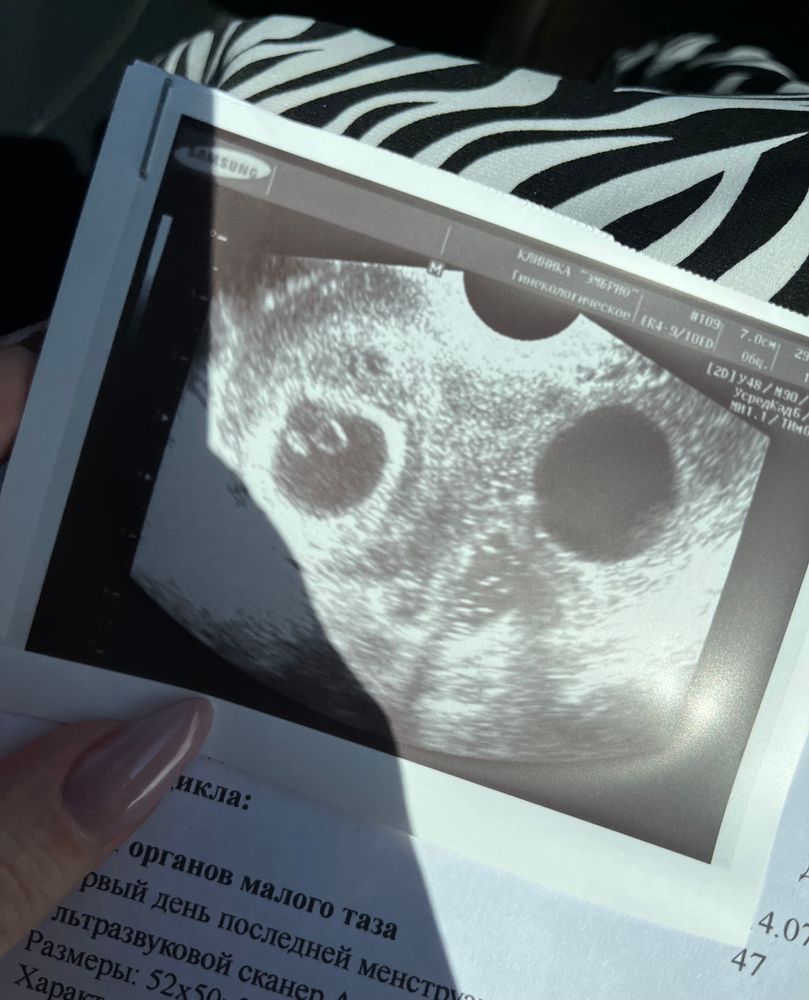

Генриетта , а у меня не можете предположить? (Сегодня была на узи, срок 6нед 3 дня, или у меня рано еще) Изображение

Алена, к сожалению непонятно, вроде как тест работает с ктр от 0.5 до 1 см. И вот вверху должно быть полукольцо, чтобы понять, с какой стороны, а здесь фото увеличено

Генриетта , поняла, у меня только еще 6нед 3 дня, и ктр 4мм🙏но сердце стучало на весь кабинет🥰